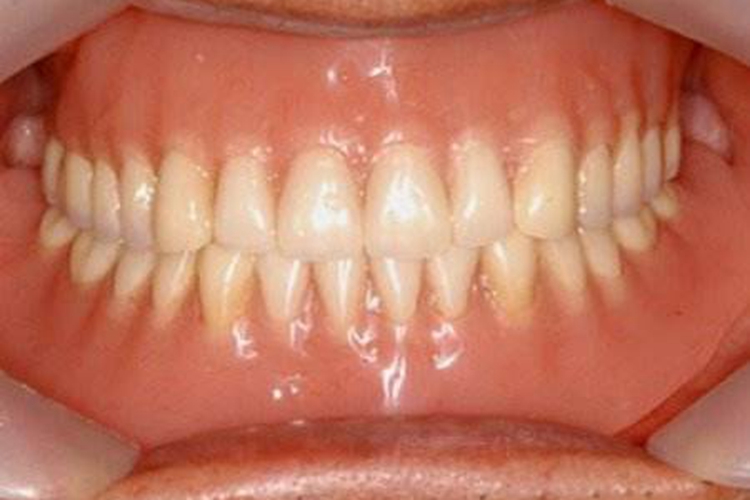

牙槽骨是上下颌骨包围和支持牙根的突起部分,骨质较疏松,且富于弹性,是支持牙的重要组织。容纳牙根的窝称牙槽窝,在冠方的牙槽窝的游离端称牙槽嵴。牙槽嵴的形态在前牙区为圆柱状,磨牙区为扁平状,而在颊舌侧变薄甚至消失。牙槽骨从X线片中,可以观察到邻间牙槽骨的高度和外形。